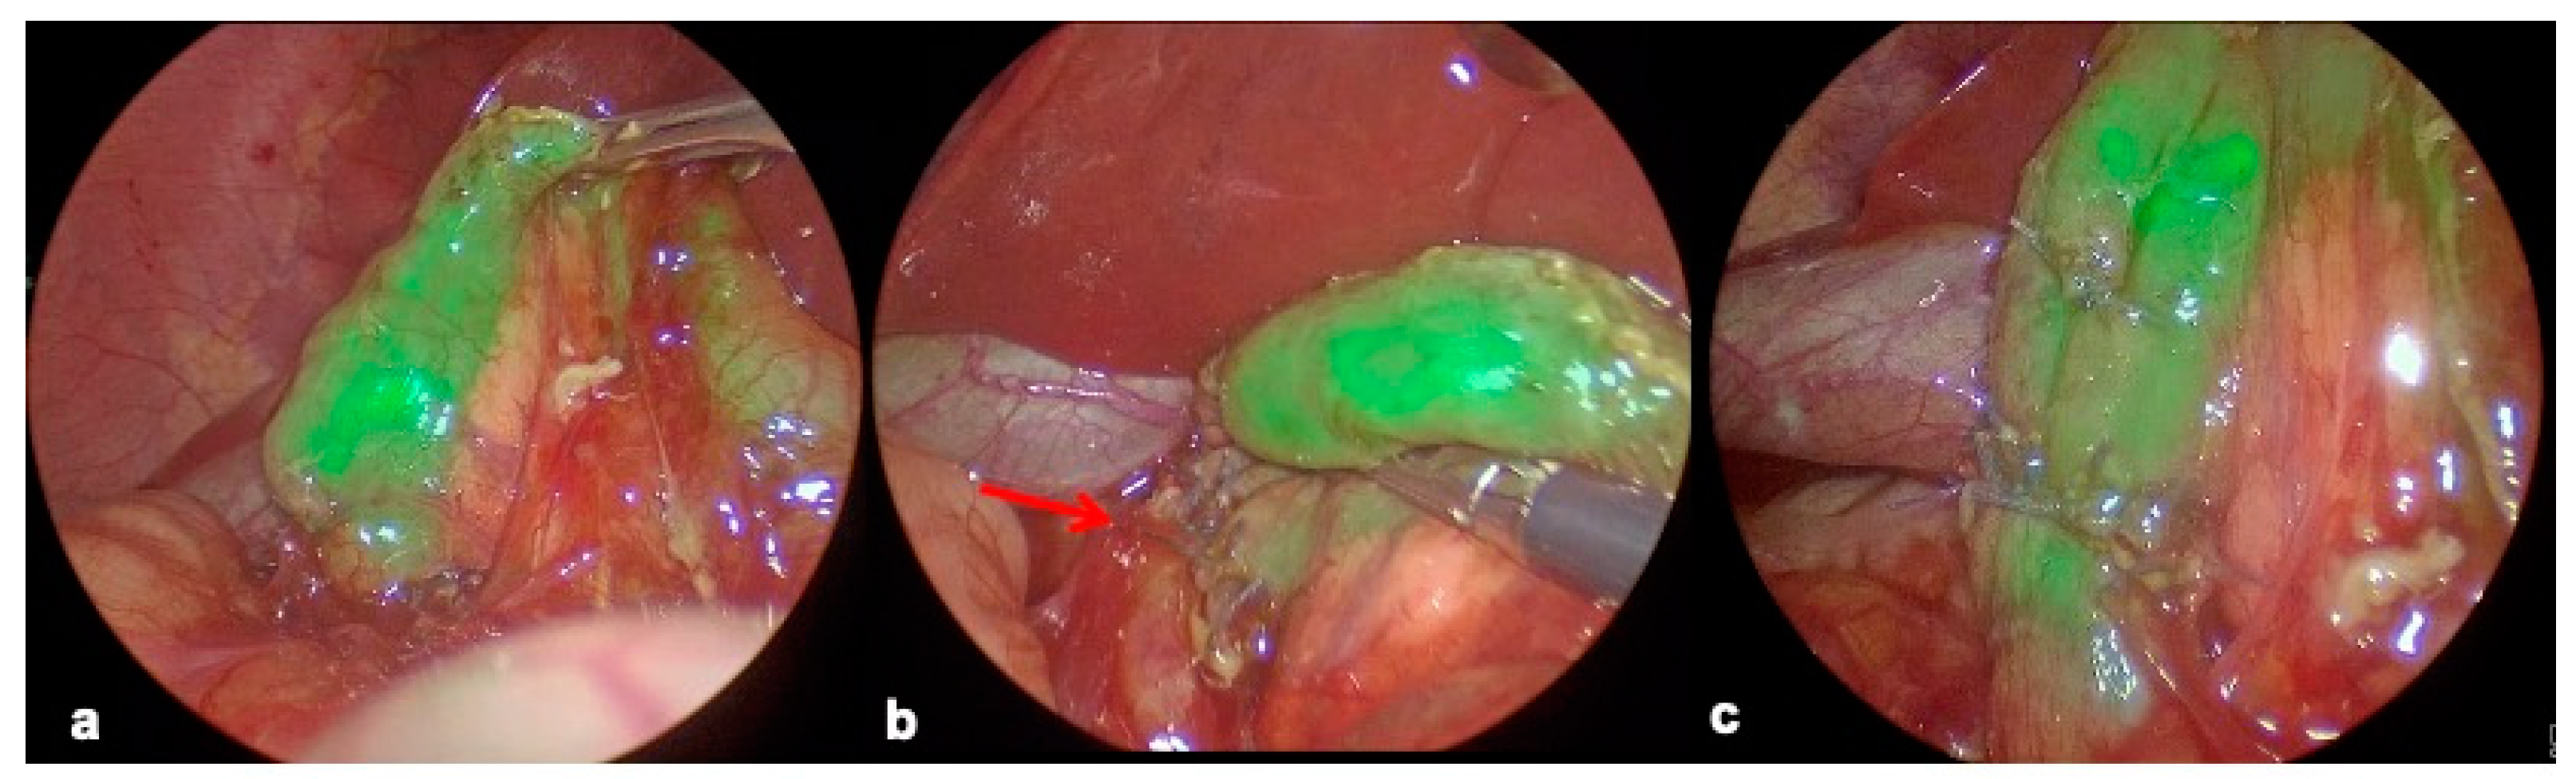

2.4.3. Duodenal Web Localization